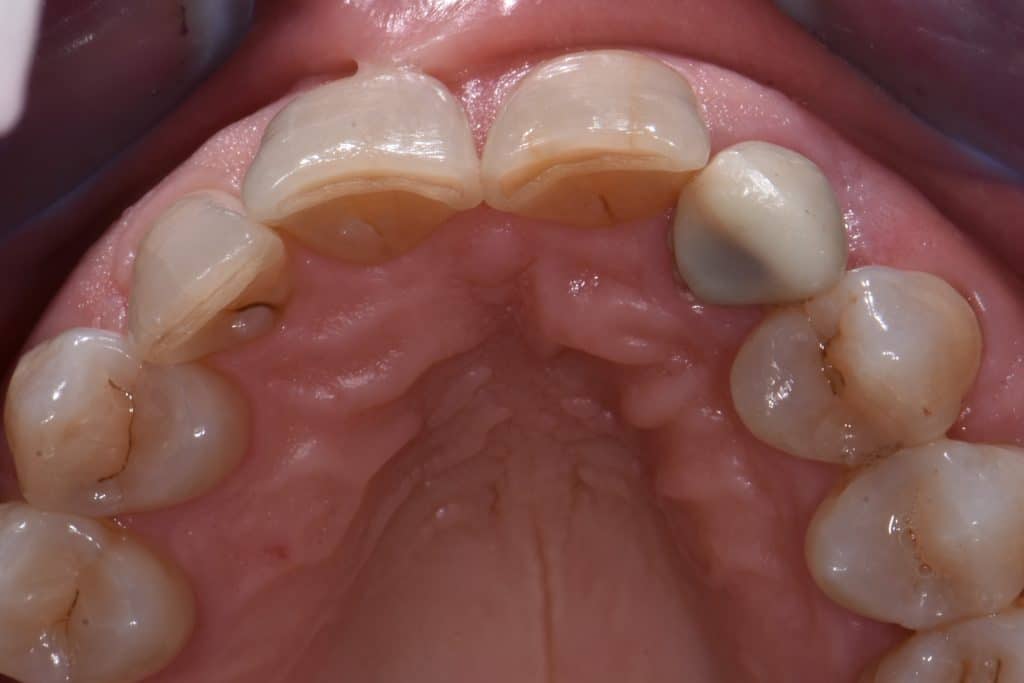

La pz N.G. di anni 52 (ASA 1) viene visitata nel mese di settembre 2017 per la mobilità ed inestetismo dell’elemento protesico 22, (foto iniziali sequenza 1) si evidenzia una frattura parziale della radice, si decide per l’estrazione ( foto sequenza 2) e sostituzione dell’elemento con un restauro implanto-protesico. Purtroppo la scarsa quota ossea apicale all’alveolo post-estrattivo (foto 2 rx) e l’alta valenza estetica dell’elemento ci rende cauti e si programma una socket preservation post estrattiva con l’ausilio delle membrane di prf (foto prf e socket sequenza 3 e 4). Durente i 5 mesi di guarigione la pz porta una protesi parziale mobile (foto 5,2) , a guarigione del sito post estrattivo si evidenzia una buona conservazione dei volumi osseo-gengivali,(foto guarigione sequenza 6) se pur presente una recessione distale all’elemnto 21.Nel mese di febbraio 2018 si procede all’inserimento di un impianto max-stability 3,75x12mm disegnando un lembo anticipato palatino per consentire un aumento dei tessuti vestibolari suturando con tecnica rool flap e trasformando l’elemento parziale mobile in una corona singola a carico immediato sul moncone temporameo applicando i concetti protesici bopt , (foto impianto moncone protesi provvisoria sequenza foto 7-8-9). Durante il periodo di maturazione dei tessuti molli vengono apportate opportune modifiche ai profili del provvisorio al fine di dare maggior spazio al tessuto gengivale, ( fotosequenza 10).Dopo circa 2 mesi dal protesizzazione provvisoria si è proceduto alla realizzazione del manufatto protesico con tecnica chair side sirona con l’ausilio del t-base (foto sequenza 11-12-13), realizzando in una sola seduta una corona in disilicato, ottenendo un risultato più che soddisfacente (Foto 14). Nel controllo a 3 mesi dal carico definitivo si apprezza la perfetta conservazione dei livelli ossei e gengivali. (foto sequenza 15).concludo con un follow up a 18 . Tengo a sottolineare che un caso come questo è stato conducibile con buoni risultati solo grazie alla piena fiducia della pz e alla sua massima motivazione e collaborazione. Ad oggi la pz sorride soddisfatta del risultato. E questo rappresenta la massima ricompensa di chi dedica tutto se stesso alla professione.